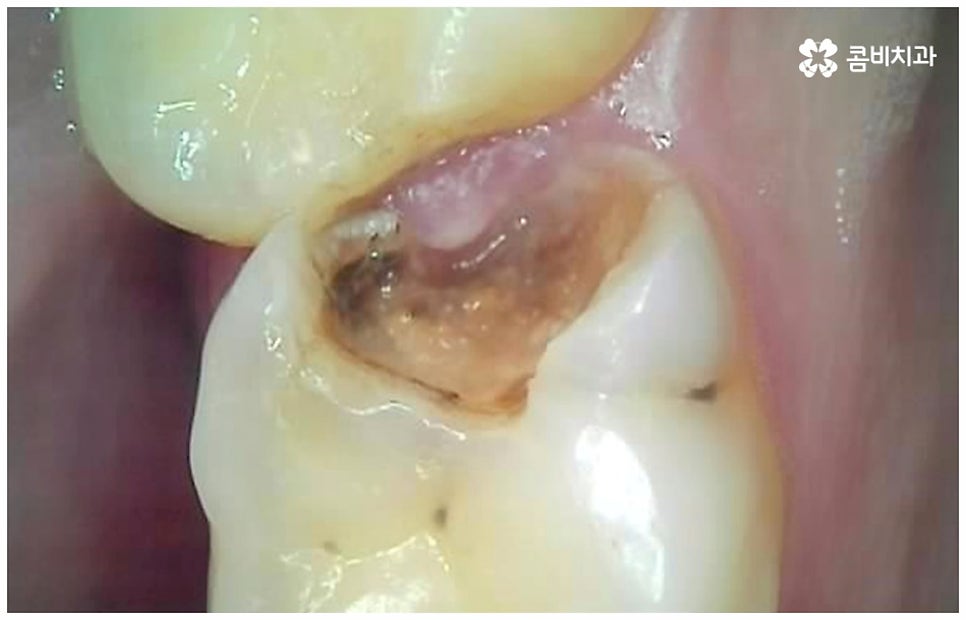

여기서 어금니신경치료 란 법랑질과 상아질을 지나 치아 안쪽 깊은 곳의 치수 조직까지 감염이 되었을 때 손상 부위를 모두 제거하고 치근관을 소독, 밀폐하는 치료를 의미하고 있는데요. 사람의 치신경은 아주 얇고 치근관의 모양과 개수는 모두 다 다른데 만약 끝이 구부러져 있거나 미세 부근관이 여러 갈래로 많이 퍼져 있는 경우, 신경관이 막힌 경우라면 신경을 제거할 때 난이도가 올라가므로 더욱 주의깊게 치료할 필요가 있어요.

감염 조직을 완전히 제거하지 않으면 통증이 지속될 수 있고 재발 가능성 또한 높아지므로 어금니신경치료 시 담당의 선생님의 높은 숙련도 및 세심한 기술력이 요구되고 있는데요. 혹시 모를 부작용을 방지하기 위해 3D CT 와 같은 정밀 진단 기계를 갖추고 신경관의 위치와 모양, 환자분들의 골조직 및 치아까지의 거리 등을 꼼꼼하게 파악하여 치료 계획을 세운 후 손상 부위를 세심하게 제거한다면 고난도의 경우라도 보다 안전하게 진행할 수 있어요.

어금니는 위치상 구강 내 가장 안쪽에 위치하므로 평상시 양치질을 잘 해 준다고 해도 음식물 찌꺼기가 남아있을 가능성이 커 충치 발생률이 높은 치아라고 할 수 있는데요. 이렇게 충치로 인한 손상 때문이 아닌 다른 이유로 어금니신경치료 를 진행해야 하는 경우도 있을 수 있어요. 예를 들어 20살 전후로 사랑니가 나오면서 삐뚤어지거나 일부가 매복된 채로 비정상적인 맹출을 하게 되면 앞의 어금니 뿌리에 압박을 주는 등 좋지 않은 영향을 줄 수 있는데요. 이 때 바로 사랑니를 발치하지 않고 그대로 방치한 채 시간이 오래 흘러 어금니까지 손상이 생겼을 경우 어금니신경치료 를 받아야 할 수 있어요. 그밖에도 외부에서 큰 충격을 받아 어금니가 깨지거나 부러져서 드물게 신경이 노출된 경우에도 감염된 신경 제거가 필요할 수 있는데요.